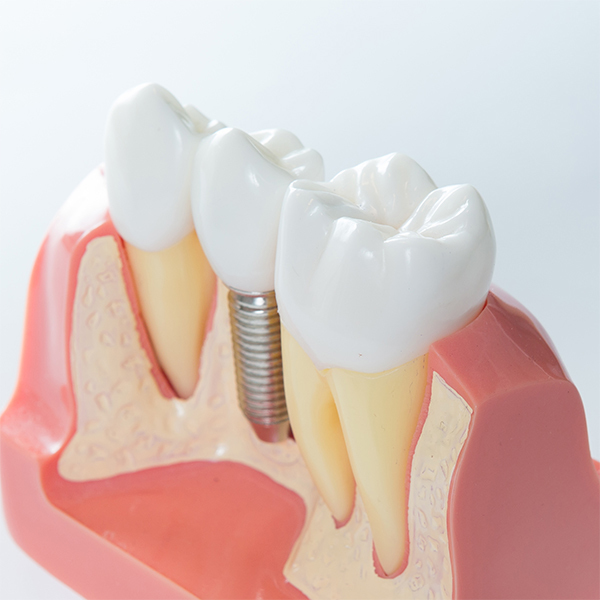

インプラント埋め込み

失われた歯のあごの骨に、チタン製の人工の歯根(しこん:歯の根)を埋め込む手術です。最終的には人工の歯(被せ物)を被せ、しっかりと噛めるようにします。

インプラント

埋め込み

¥300,000